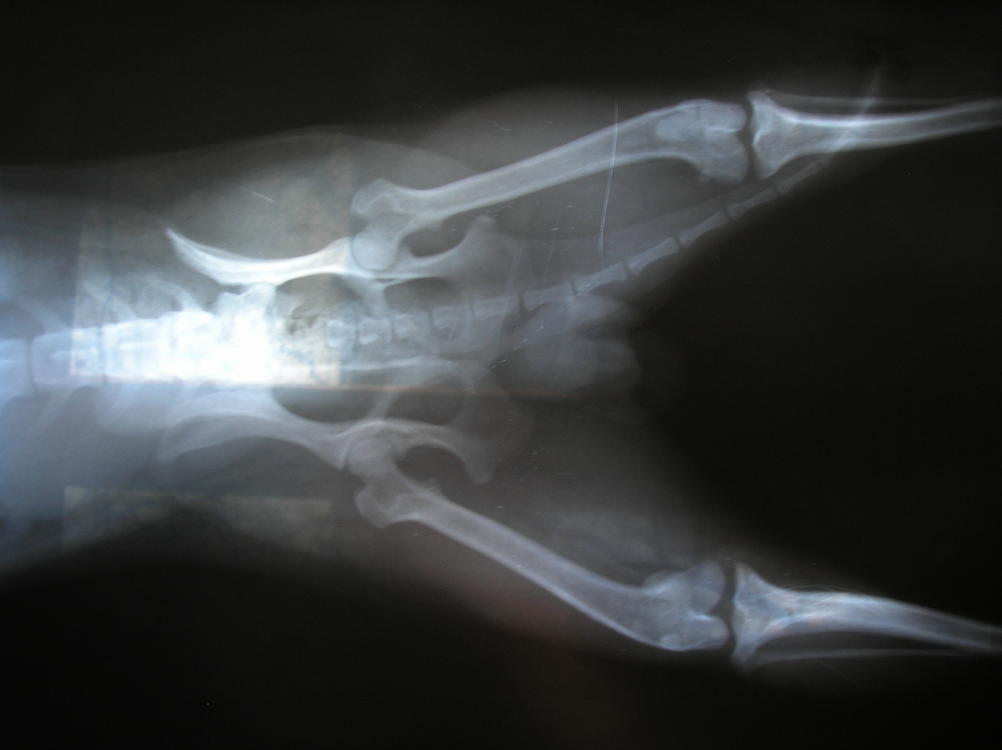

Снимки очень плохого качества и сделаны не правильно ( обязательно нужно, что бы две лапы были на снимке в позе лягушки , собака при этом лежит на спине, с захватом бедренных суставов), по этому по состоянию сустава конкретно, к сожалению, ничего не скажу.

Но со связками есть проблема - явно. Вывих пателлы не исключен, но и подтвердить его только снимками, тем более такого качества не возможно.

Снимки намного лучше, видно, по крайней мере, что с суставной поверхностью, судя по ним - проблем нет ( как в коленном, так и в бедренном суставе).

А вот проблему со связками и смещением коленной чашечки - исключить не могу, к сожалению. Равно как и подтвердить, потому что для этого требуется пальпация, обследование подвижности сустава ) .